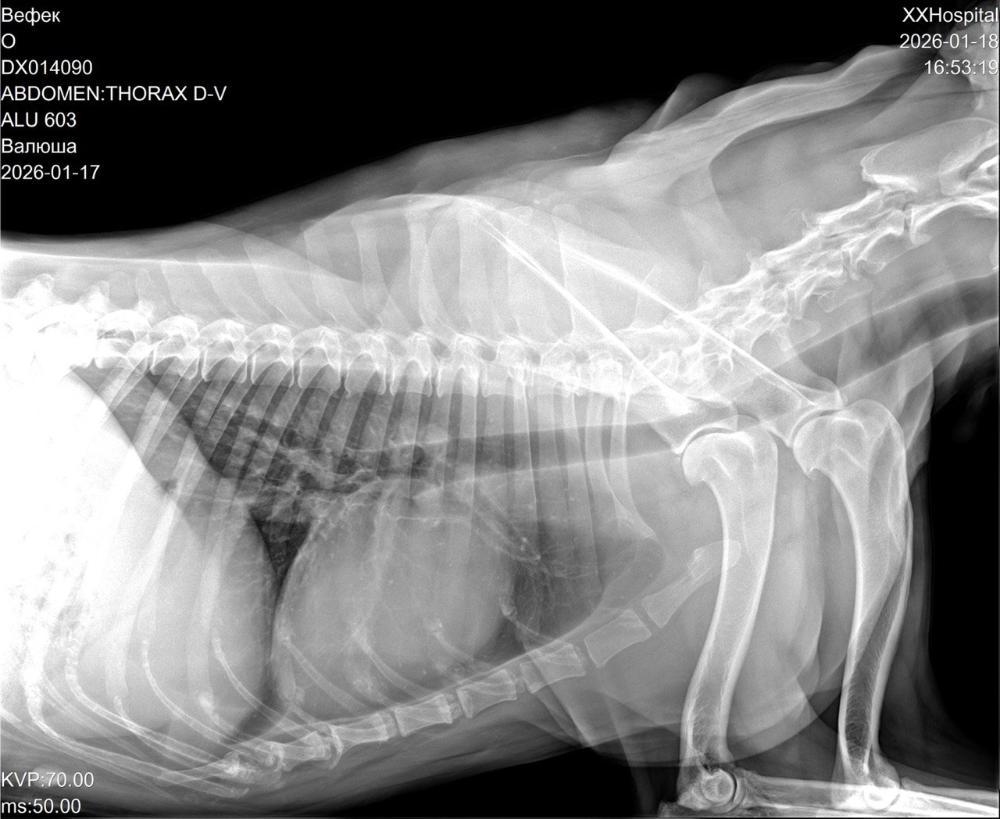

Опять испытание для Валюши - н/о молочной железы, готовимся к операции😢Девчушке нужна наша помощь и поддержка! Куратор Вячеславовна